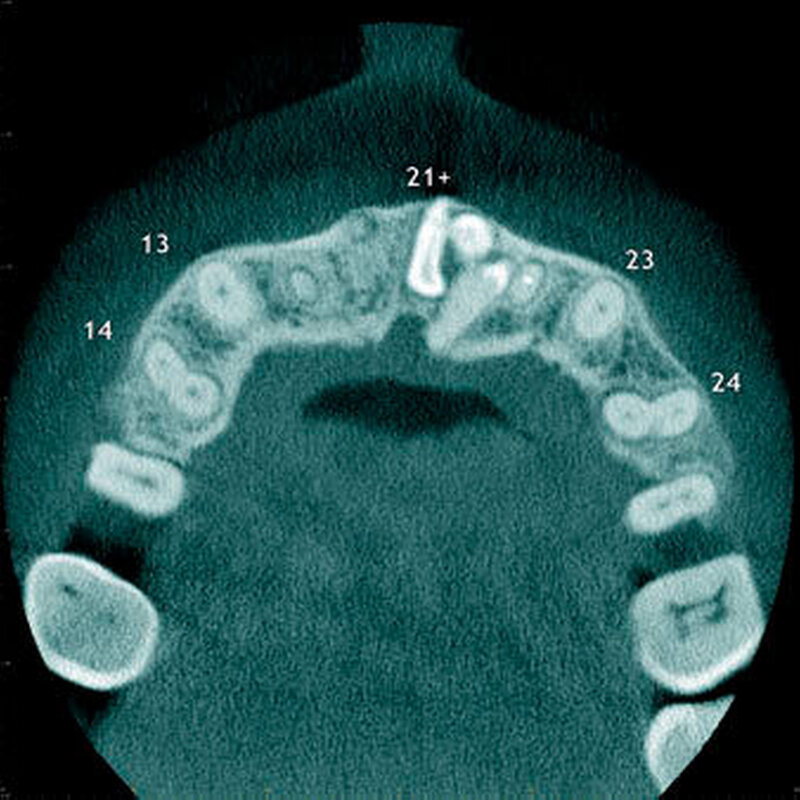

Überzählige Zähne können einzeln oder multipel auftreten [von Arx, 1990; Rajab Hamdan, 2002; Fernández Montenegro et al., 2006; Liu et al., 2007; Gündüz et al., 2008; Ferrés-Padró et al., 2009; Hyun et al., 2009]. Einzelne überzählige Zähne treten in 65,8 bis 80,5 Prozent, doppelte in 14,5 bis 27,7 Prozent und multiple in 0,6 bis 8 Prozent der Fälle auf [Rajab Hamdan, 2002; Fernández Montenegro et al., 2006; Liu et al., 2007; Ferrés-Padró et al., 2009; Hyun et al, 2009; Mossaz et al., 2014]. Einzelne oder doppelte überzählige Zähne finden sich typischerweise in der Oberkieferfront [Rajab Hamdan, 2002; Fernández Montenegroet al., 2006; Mossaz et al., 2014]. Multiple überzählige Zähne werden vor allem im Prämolarenbereich des Unterkiefers gefunden [Abbildung 4; YUSOF 1990, Ferrés-Padróet al., 2009; Wang Fan, 2011]. Multiple überzählige Zähne sind zudem oft mit anderen Erkrankungen oder Syndromen assoziiert, dazu gehören Lippen-Kiefer-Gaumenspalten, die cleidokraniale Dysplasie oder auch das Gardner-Syndrom. Bei Patienten mit einer Lippen-Kiefer-Gaumenspalte wird vermutet, dass sich die überzähligen Zähne aus der Fragmentierung der dentalen Lamina bei der Spaltbildung ergeben [Garvey et al., 1999; Wang Fan, 2011].

Überzählige Zähne werden nach ihrer Lage im Zahnbogen und auch aufgrund ihrer Morphologie eingeteilt. Basierend auf der Lage unterscheidet man bei überzähligen Zähnen zwischen Mesiodens (Oberkiefer median), zwischen den zentralen Inzisiven (Abbildungen 5 und 6), einem zusätzlichen Schneidezahn (zentral oder lateral), Eckzahn, Prämolar (Abbildung 7), Paramolar und Distomolar (Abbildungen 8). Mesiodentes werden am häufigsten dia- gnostiziert, wobei Prozentsätze zwischen 38,8 Prozent bis 86,3 Prozent der überzähligen Zähne in der Literatur zu finden sind [Salcido-García et al., 2004/38,8 Prozent, Fernández Montenegro et al., 2006 /46.9 Prozent; Mossaz et al., 2014/48.5 Prozent; Ferrés-Padró et al., 2009/53.2 Prozent; Schmuckli et al., 2010/75 Prozent; Rajab Hamdan 2002/83.2 Prozent; Liu et al., 2007/86.3 Prozent]. Überzählige Prämolaren und seitliche Schneidezähne sind die zweithäufigste Gruppe der überzähligen Zähne. Überzählige Eckzähne, Paramolaren und Distomolaren dagegen gelten als eher selten [Rajab Hamdan, 2002; Salcido- García et al., 2004; Liu et al., 2007; Ferrés-Padró et al., 2009; Schmuckli et al., 2010; Mossaz et al., 2014]. Einzig eine Spanische Gruppe [Fernández Montenegro et. al., 2006] berichtete, dass Paramolaren und Distomolaren insgesamt relativ häufig seien (18 Prozent, beziehungsweise 5,6 Prozent). Überzählige Zähne kommen im Ober- und Unterkiefer vor, wobei sich überzählige Schneidezähne in der Regel im Oberkiefer, überzählige Prämolaren sich dagegen eher im Unterkiefer befinden [Fernández Montenegro et al., 2006; Ferrés-Padró et al., 2009; Mossaz et al., 2014]. Überzählige Molaren wiederum treten normalerweise im Oberkiefer auf [Cassetta et al., 2014; Kaya et al., 2014].